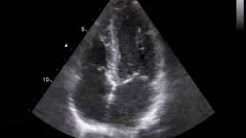

第37回 市民公開健康講座(2015年12月17日開催) 「心不全」ってどんな病気?心エコー法で診る ・心不全の症状 ・心臓の働き ・急性と慢性

大分県立病院 循環器内科 http://hospital.pref.oita.jp/consult_introduction_jyunkanki/ 心不全の一部には心臓の収縮が一様ではない(同期